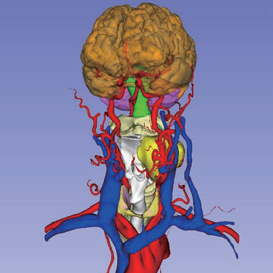

(根据CT图像,重建了肿瘤、动脉、静脉、大脑、小脑、甲状腺、骨骼、气管、神经等模型)

三维重建中病灶位置信息

三维重建头颈系统动静脉整体预览

三维重头颈系统整体预览